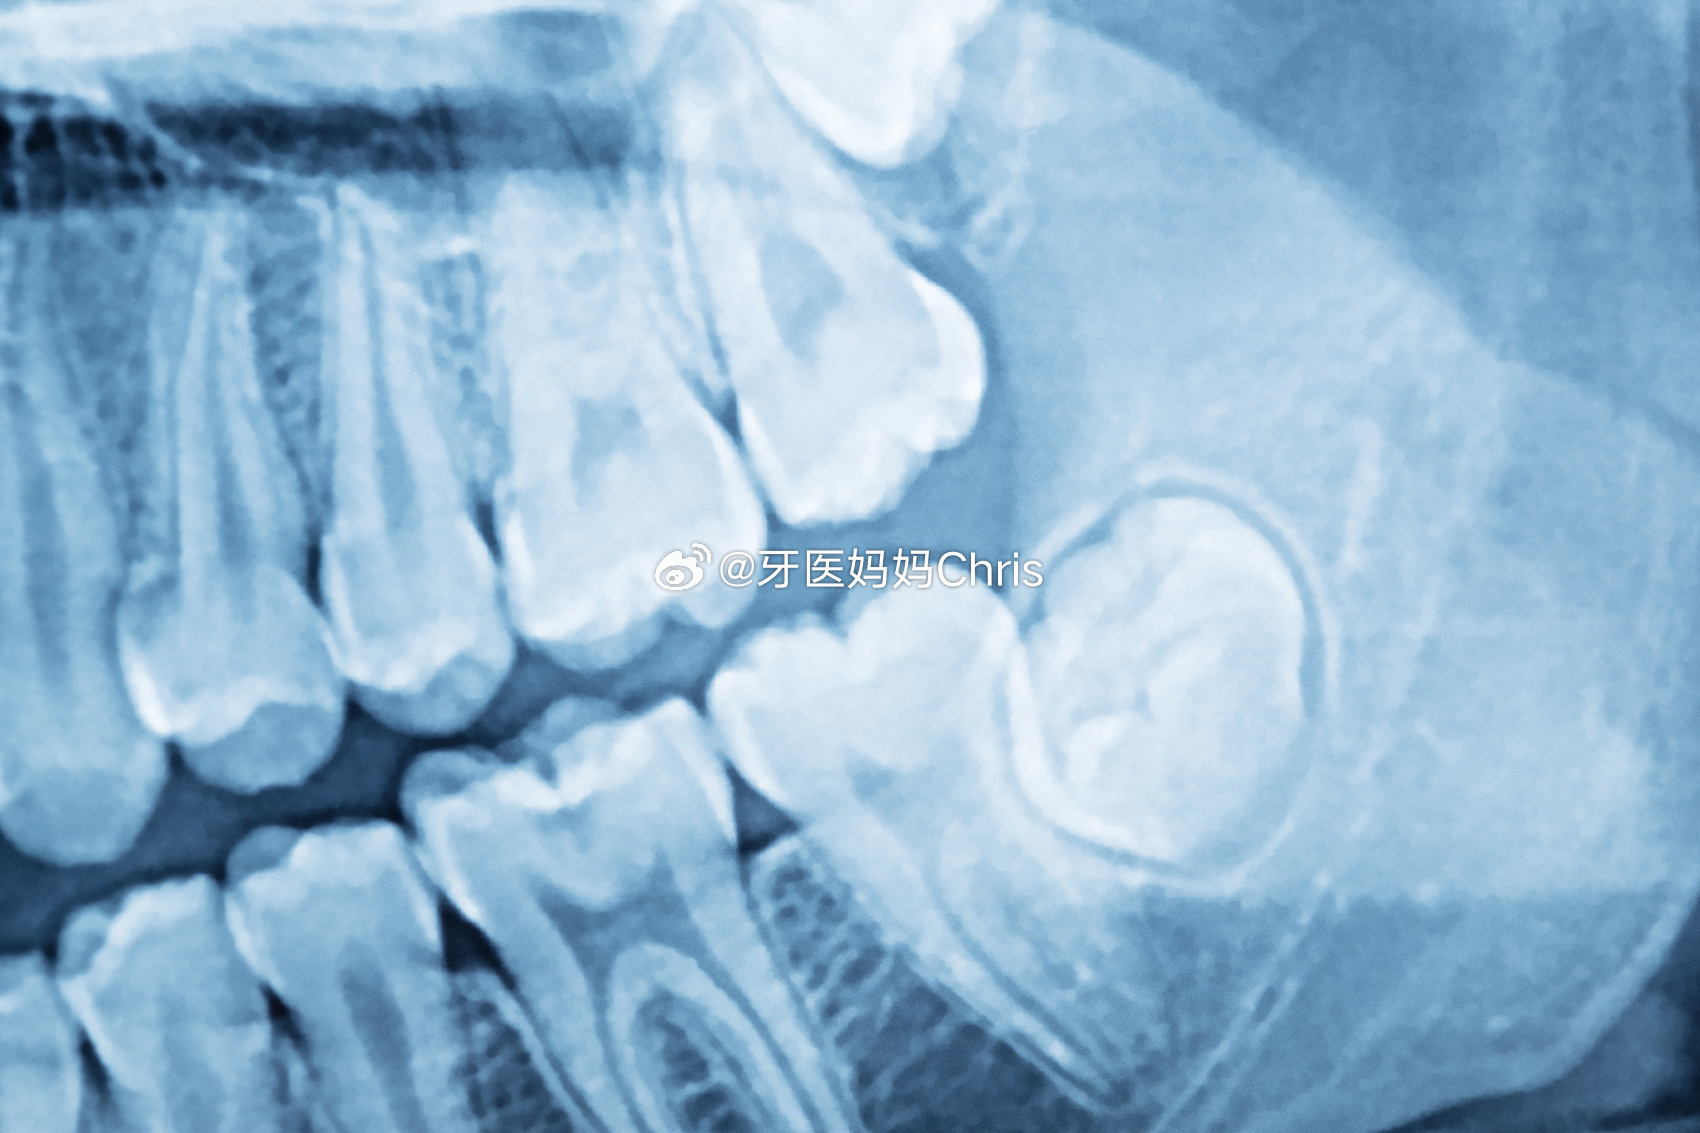

有的智齿因为颌骨发育不足,缺乏足够的空间以致不能完全萌出,就形成了阻生智齿。

通俗点说就是牙齿埋在骨头里长不出来了。

低位埋伏的阻生智齿有可能发生病变导致其他牙源性问题。